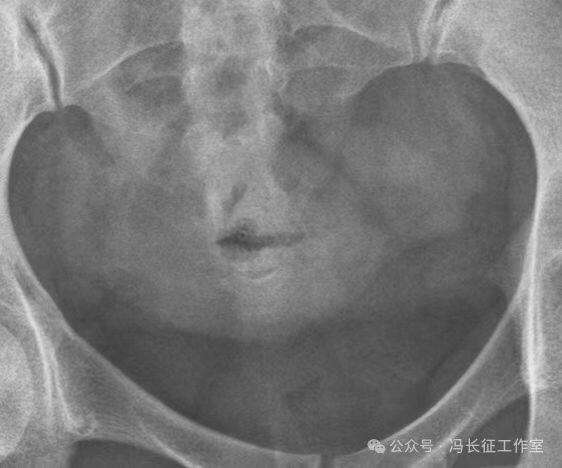

下面是一例正常子宫输卵管造影图(4张片)

微信图片_20240215160254.jpg